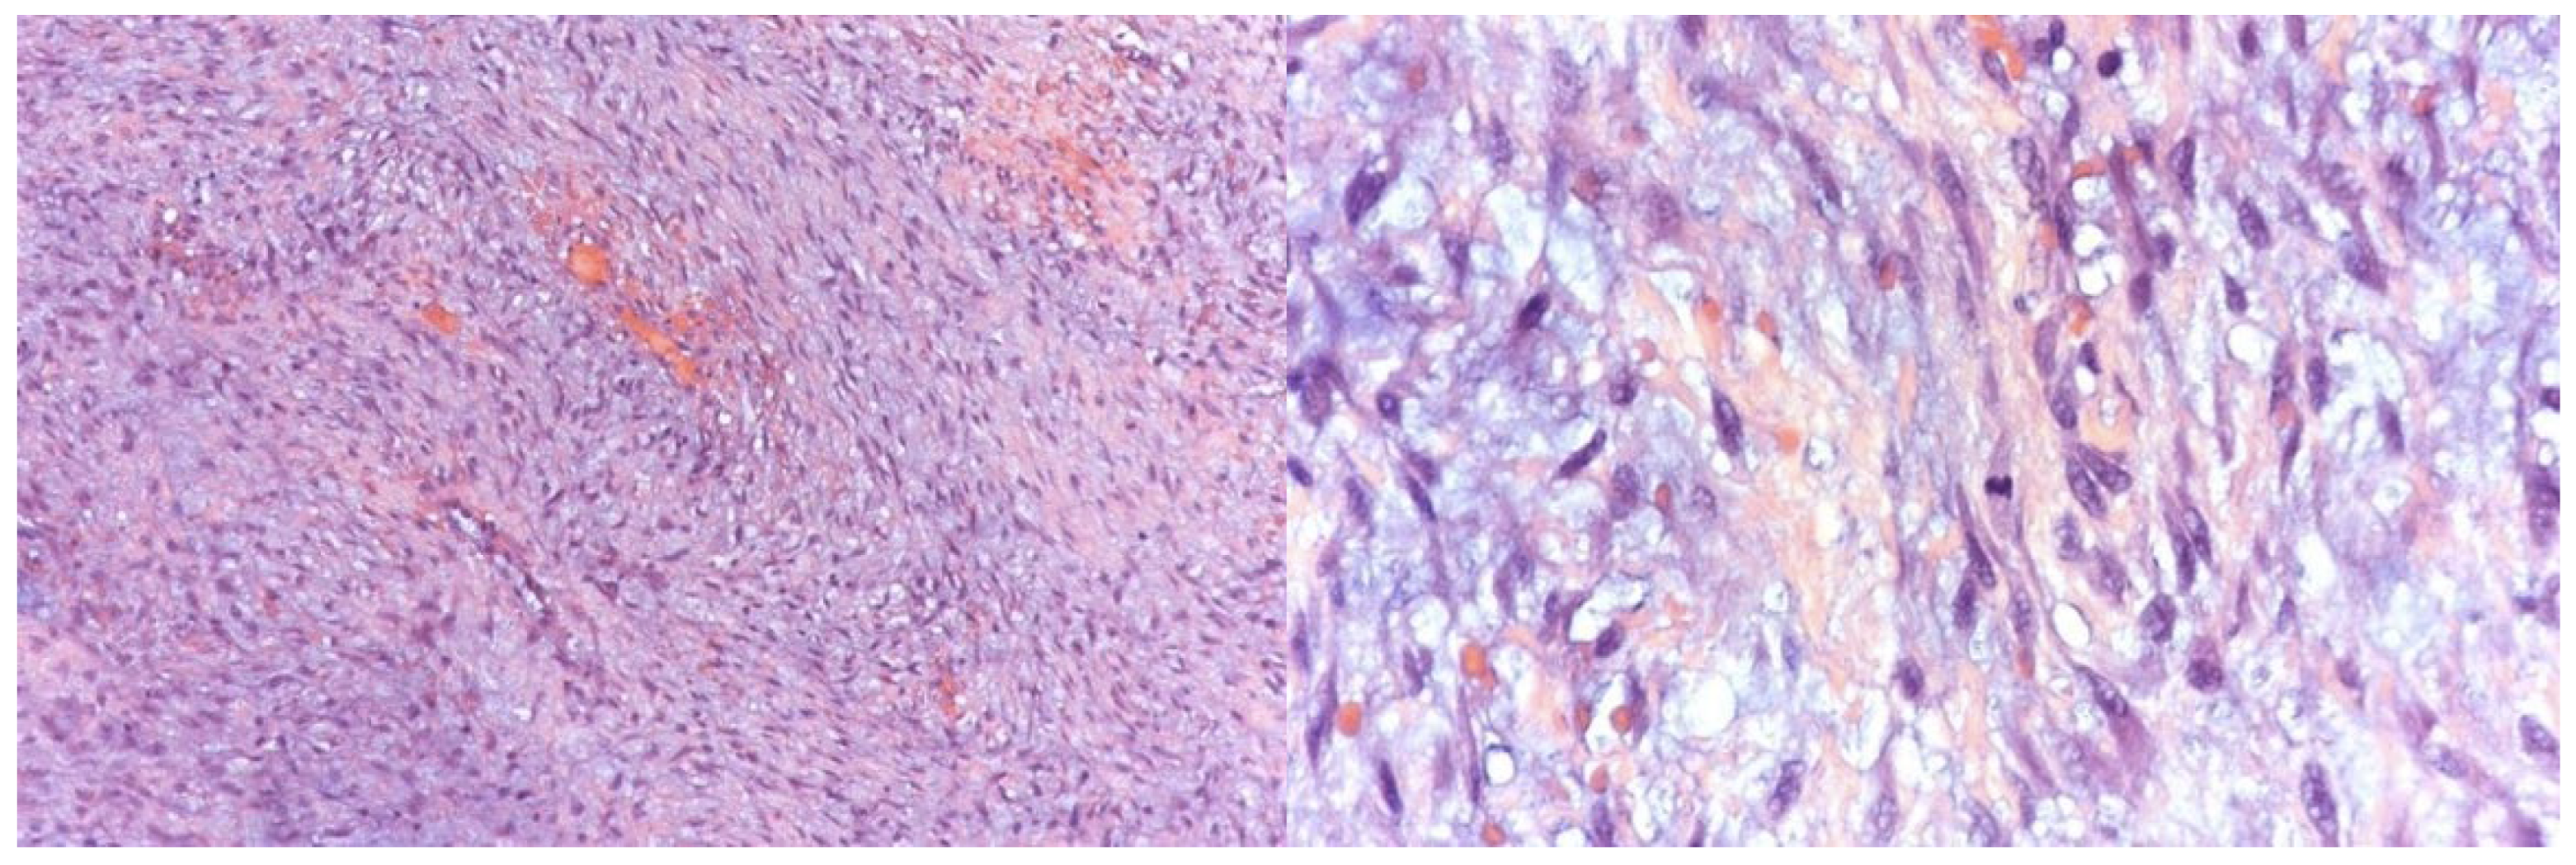

Histopathological examination confirmed a benign mesenchymal tumor composed of monomorphic spindle cells arranged in short, interwoven bundles within a diffusely myxoid stroma (Figure 3). The mitotic index was low (1 mitosis per 10 HPF), with a Ki67/MIB1 proliferation rate of 7%. Immunohistochemistry revealed weak diffuse positivity for CD99, while all other markers tested (p63, CD34, CD68/PGM1, S-100, EMA, MUC-4) were negative. No necrosis was present, and fragments of bone tissue were observed interspersed with tumor cells.

Figure 3. Histological examination of tumor sections under light microscopy demonstrating features suggestive of an odontogenic myxoma.